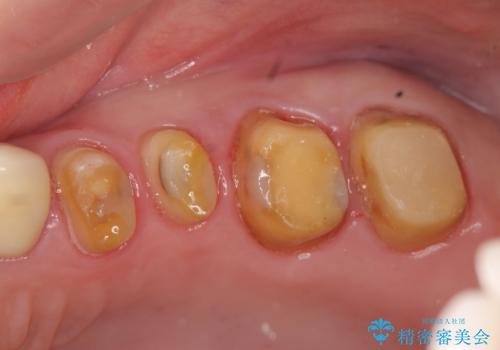

奥歯の被せ物のやり直し 精密根管治療

- 左上の一番奥の歯の根の治療を行いつつ、手前の歯の被せ物のやり直しも一緒に行いました。

手前の被せ物は、メタルボンドクラウンだったため、歯ぐきとの境目が黒くなっていたためやり直しを行いました。

オールジルコニアクラウンに変え、審美的な被せ物になりました。